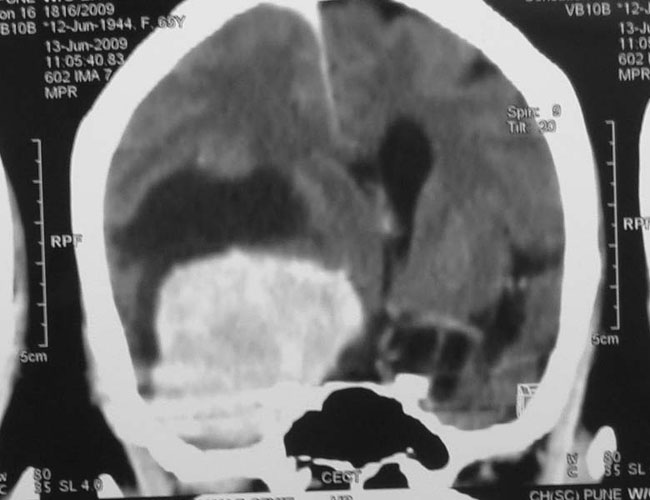

Arteriovenous malformations

Arteriovenous malformations of the brain are abnormal bunch of blood vessels that can rupture causing bleeding, or may cause seizures. Brain imaging (CT, MRI) is required for early diagnosis, while definitive treatment is carried out after cerebral angiography. Treatment implies craniotomy and excision of the AVM, which can be done safely in majority of the cases. Embolisation and radiosurgery are acceptable substitutes, but carry risk of further bleeding.